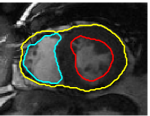

V-C LV and RV Segmentation: Quantitative Comparison to Commercial Software

We show experiments demonstrating the main use of our algorithm: in improving the prediction step of interactive segmentation methods. We show that less interaction is needed with our approach than a recent and widely used commercial cardiac segmentation software, Segment from Medviso [15, 44]. We perform quantitative assessment of the tracking performance of our method and compare it to Medviso. The evaluation was carried out on publicly available data sets, the MICCAI Left Ventricle Dataset [37] and the MICCAI Right Ventricle Dataset [25]. The validation dataset from [37] consists of 15 sets of cardiac cine-MRI images. Each set contains 6 to 20 2D slices from a 3D image, with each slice having 20 images of the cardiac phases. Similarly, the data set [25] contains 16 sets of cardiac cine-MRI images, each containing about 10 slices of 20 phases each. These data sets contain ground truth segmentations for left and right ventricles respectively (unfortunately ground truth for both the LV and RV is not available on a single dataset that we are aware of). Both methods start with the same initially correct segmentation, and subsequent frames are segmented via propagation. No manual interaction is used as we wish to show that our method would require less interaction. The regularity parameter in our method is found by choosing so that the results are closest to ground truth in a few training cases. The same parameter is then used for all other cases.

Figures 8 and 9 shows some sample tracking results of the proposed method and Medviso on full cardiac cycles of two different cases on both the LV dataset and the RV dataset. The ground truth (yellow) is superimposed when available. A summary of the results on the entire datasets is shown in Table I. The accuracy with respect to ground truth is measured using average perpendicular distance (APD) and dice metric (DM) for left ventricle, and Hausdorff distance (HD) and DM for the right ventricle. These metrics are chosen since they are the standard ones used on these datasets. Both qualitative and quantitative results show that our proposed method leads to more accurate segmentation of the ventricles and thus leads to less interaction than segmentation propagation schemes in than Medviso.